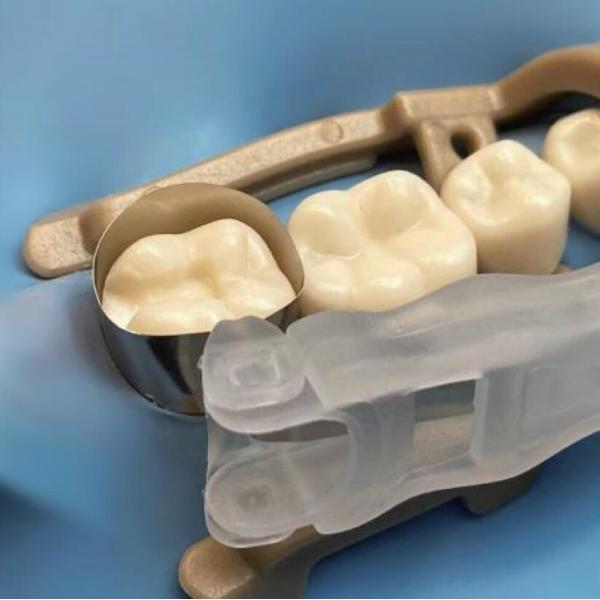

Dental Sectional Matrix System Retainer and Matrix M5 2.0

Retainer and Matrix M5 2.0

Curved to any angle, suitable for tooth shape, tighten toward gingival, fit tightly without overhang.

The head can be adjusted at any angle of 180 degrees, suitable for any tooth position in each quadrant;

Single knob design, convenient and fast operation, firm tightening and no slipping;

The ultra-thin polished matrix bands, fitting tooth body better.

| Order No. | Specification | Package |

| DMB1204 | 6.2mm 0.001" (0.025mm) Yellow SS Curve Wingless | 24 pcs/box |

| DMB1205 | 6.2mm 0.0015" (0.038mm) Light Green SS Curve Wingless | 24 pcs/box |

| DMB1214 | 6.2mm 0.001" (0.025mm) Yellow SS Curve with Wing | 24 pcs/box |

| DMB1215 | 6.2mm 0.0015" (0.038mm) Light Green SS Curve with Wing | 24 pcs/box |

Universal Matrix Band Retainer M5 2.0 Images |